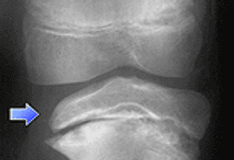

On plain radiographs, the femoral head is seen displaced, posteriorly and inferiorly in relation to the femoral neck and within the confines of the acetabulum. [9] Treatment is primarily operative internal fixation. The goal is to prevent complications such as avascular necrosis (AVN). [2, 10, 11, 12, 13]

A Klein line is a line drawn along the superior border of the femoral neck that would normally pass through a portion of the femoral head. If not, slipped capital femoral epiphysis is diagnosed.